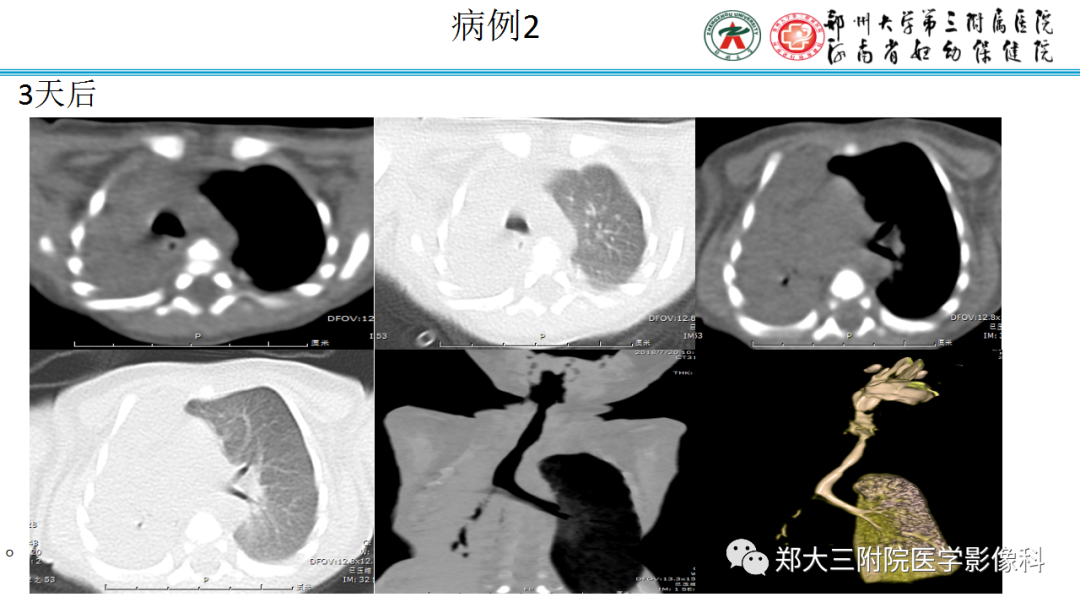

纵隔大细胞神经内分泌癌1例CT影像

纵隔大细胞神经内分泌癌1例CT影像  张力性纵隔气肿影像表现及严重度分级

张力性纵隔气肿影像表现及严重度分级  迅速增大的肺部结节,首先考虑良性,确诊需要肺穿

迅速增大的肺部结节,首先考虑良性,确诊需要肺穿  肺隔离症:易误诊为肺癌的占位性病变,肺穿刺禁忌!

肺隔离症:易误诊为肺癌的占位性病变,肺穿刺禁忌!  肺段与肺内管道应用解剖

肺段与肺内管道应用解剖  肺转移瘤的十种不典型CT表现

肺转移瘤的十种不典型CT表现  肺内淋巴结的CT表现特点及与病理对照

肺内淋巴结的CT表现特点及与病理对照  肺实变与肺不张的CT鉴别诊断

肺实变与肺不张的CT鉴别诊断  医生现身说法,这五种忙帮不得!